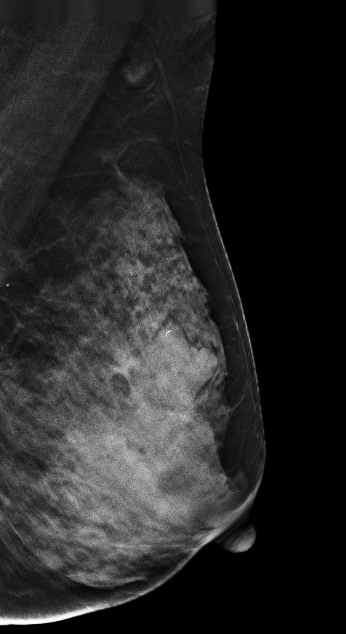

V-preview图像:

在常规2D图像右乳外上象限隐约见一不规则团块影,部分边界模糊(容易漏掉),边缘可见粗大钙化灶,在V-Preview图像MLO位和CC位上团块显示较模糊,但钙化清晰可见,在3D-slab图像上我们可以清晰见到病灶呈分叶状改变,边缘可见蛋壳样钙化灶,周边见细线样透亮环。从以上细微征象我们可以初步判断是一良性病灶。